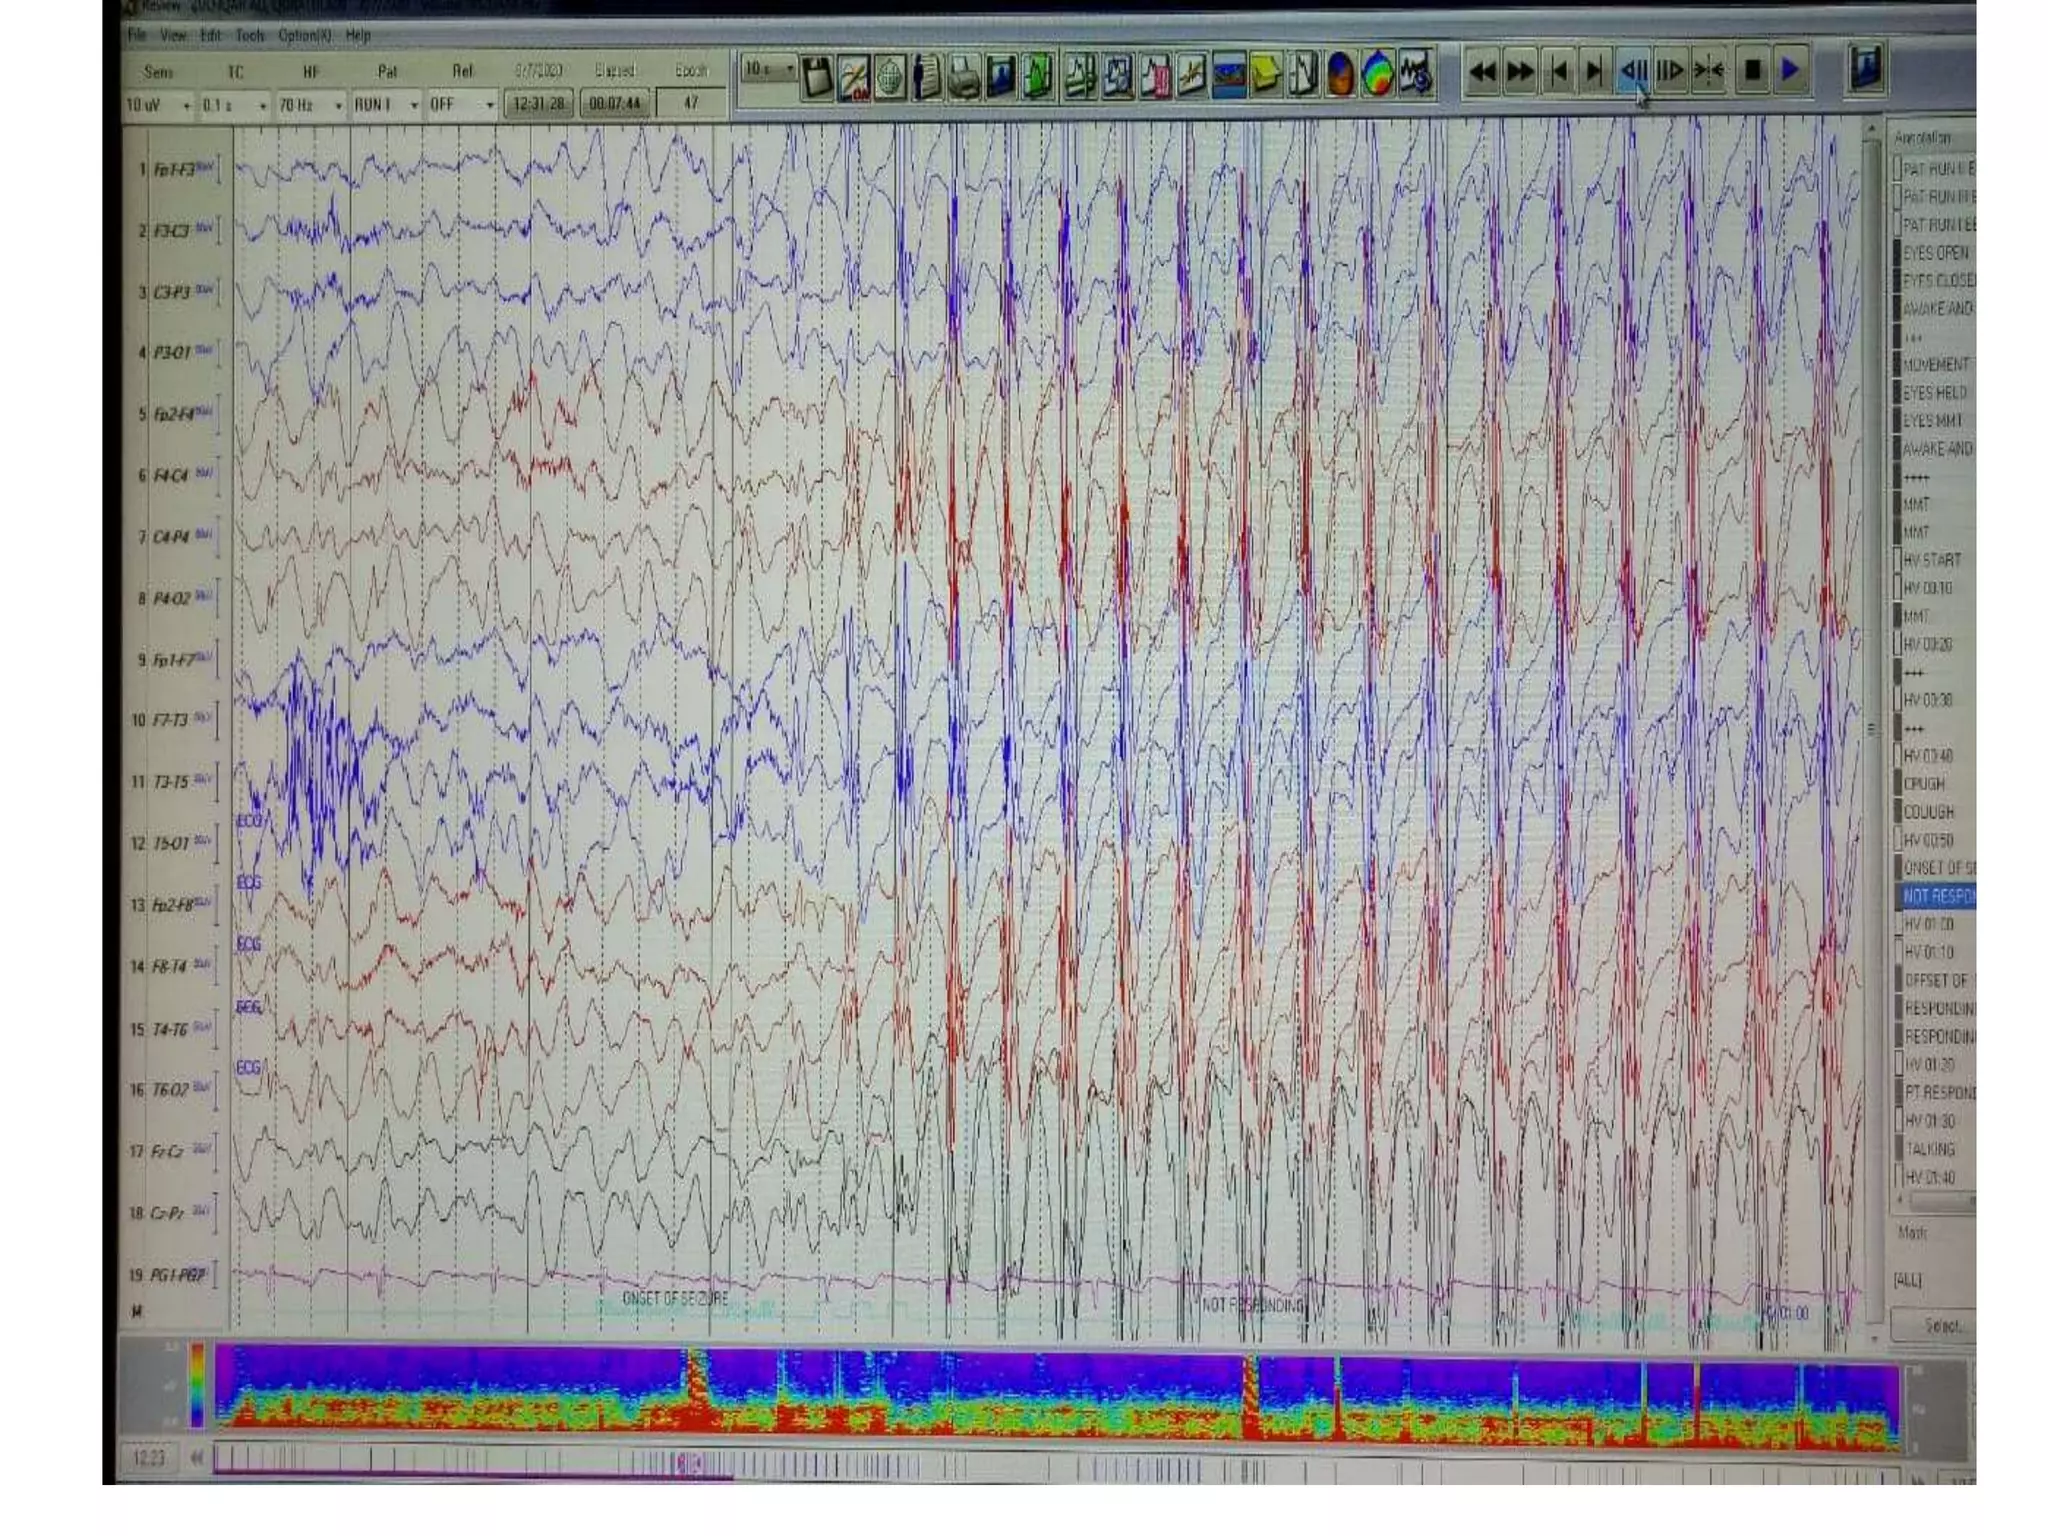

ABSENCE SEIZURES

The three Hz spike and wave pattern is suggestive of

idiopathic Generalized epilepsy.

• Characteristics:

It is classically described with typical absence epilepsies when bursts

of 3Hz spike and wave is Gen, regular, symmetrical, synchronous and

maximal in the anterior head region

Clinical symptoms: fluttering of eyes and automatism.

It usually occurs in patients aged b/w 5-12 years.

Onset : At 2 years and can be appeared till 14 years.

• Often faster at onset and slows down toward end.

• Accentuated (more prominent) by HV (50-80% pt) and photic

stimulation (about 20% of pt).